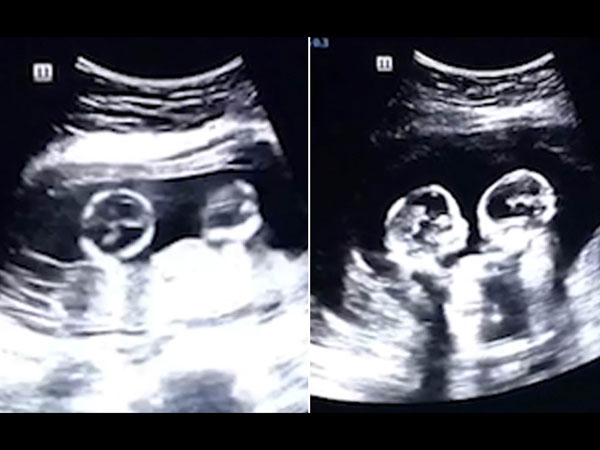

இந்தியாவின் நாக்பூரைச் சேர்ந்த 36 வயதான சஞ்சு பகத், தனது பெரிதாக்கப்பட்ட வயிற்றைப் பற்றி எப்போதும் யோசித்துக் கொண்டே இருந்தார். 1999 ஆம் ஆண்டில், அப்பெண் தனது இரட்டை சகோதரனை வயிற்றுக்குள் சுமந்திருப்பது கண்டுபிடிக்கப்பட்டது. அதுவும் வயிற்றிற்குள் சிறுவன் பாதி உருவான உடலைத் தவிர வேறில்லை.